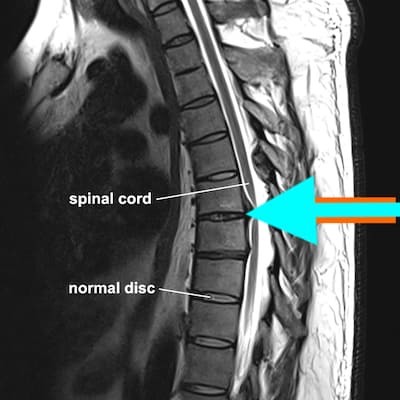

Магнитный резонанс позвоночника груди является одним из самых информативных методов диагностики. Этот метод позволяет обнаружить самые маленькие патологические изменения вокруг: повреждение позвоночника, инфекционного фокуса, опухолей, изменений в строительстве и установлении кругов и ряда других явлений без повреждений здоровья пациента.

Магнитная томография на груди позвоночна для обнаружения локальных патологий, таких как проблемы со структурой, местоположением и суставами межпозвонковых дисков, рака, инфекций и т. д. Частый симптом, что приводит к необходимости назначать диагноз, это боль.